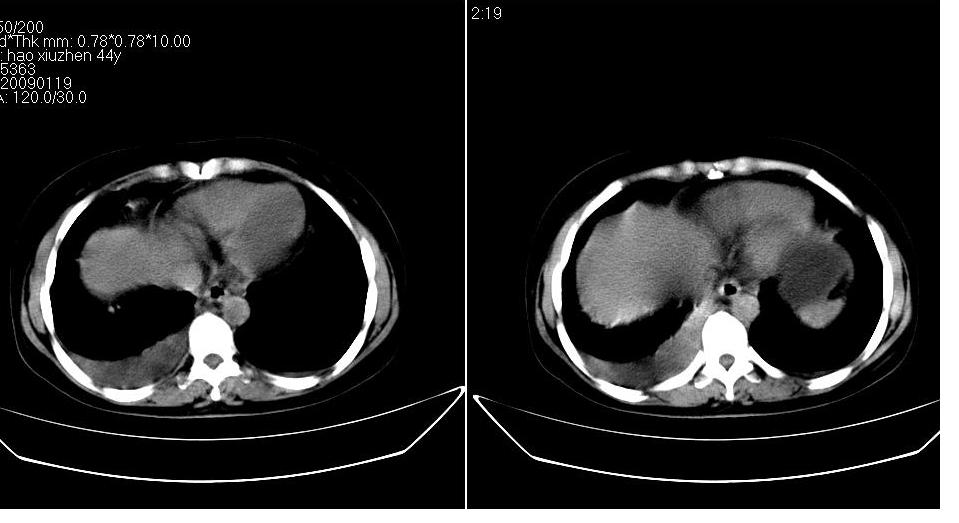

以下是引用zbp537在2009-1-19 14:09:00的发言:[br]从这个平扫图像上看,只能考虑:1、胸腹水。2、脾脏包膜下弧形高密度影,疑出血,建议复查。[br]既然腹水中有恶性细胞,建议行腹部ct增强扫描及胸部扫描。

以下是引用随光逐影在2009-1-19 15:47:00的发言:[br]1)不排除胃癌可能;建议行胃镜检查。2)腹水。3)右侧胸腔积液。

以下是引用jiangjing在2009-1-19 18:21:00的发言:[br]1 网膜污垢征---肿瘤网膜转移.2)腹水。3)右侧胸腔积液